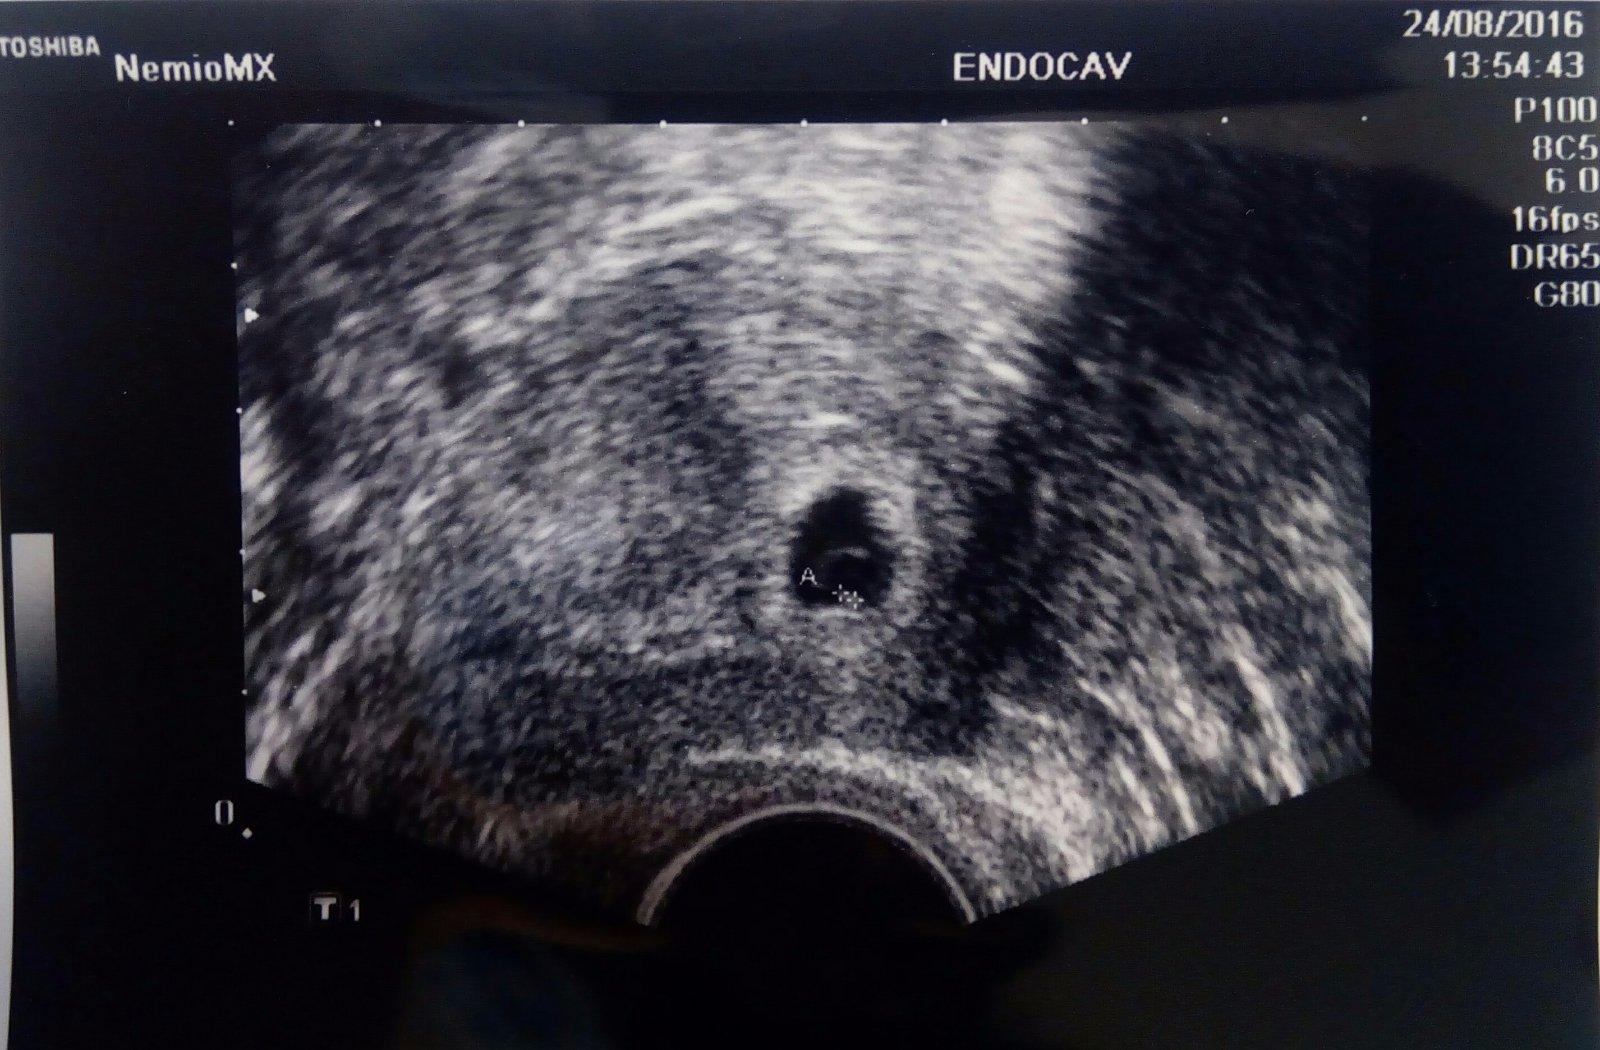

@06lienocka Na UTZ jsem byla v ukončeném šestém, teď jsem v 7tt 😉

@martaskvorova tak gratulujem si troska vpredu ja som dnes 4+3 nebola som u lekara este pockam do 8.9. asi vtedy budem 6+2

@martaskvorova ja mela v 5tt + 6 jen zloutkovy vacek a prý je to v pořádku 🙂 tak bych se nebála...

@martaskvorova ja som bola prvý raz na kontrole v 6+2 a mrňús podľa UZ odpovedal len 5+6 ( 2,5 mm s počínajúcou akciou srdiečka). Tak hlavu hore 😉